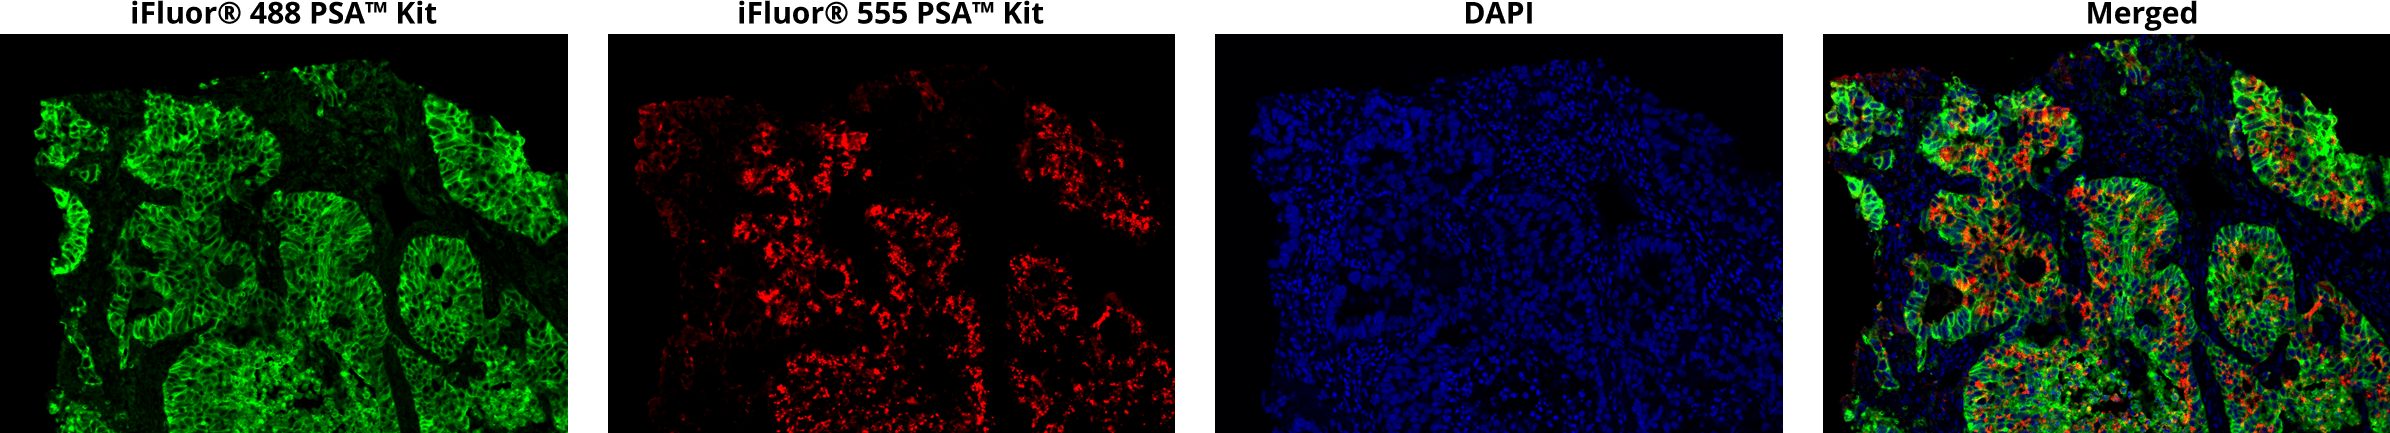

Fig. 3

iFluor® PSA Imaging kits

Sequential immunostaining of formaldehyde-fixed, paraffin-embedded human lung adenocarcinoma using iFluor® PSA imaging kits. EpCam was labeled with rabbit anti-EpCam antibody and iFluor® 488 PSA imaging kit with goat anti-rabbit IgG (Catalog Number 45205), followed by washing. Pan-keratin was labeled with mouse anti-pan keratin antibodies and iFluor® 555 PSA imaging kit with goat anti-mouse IgG (Catalog Number 45270). Nuclei were labeled with DAPI (Catalog Number 17507). Images were acquired on a confocal microscope.